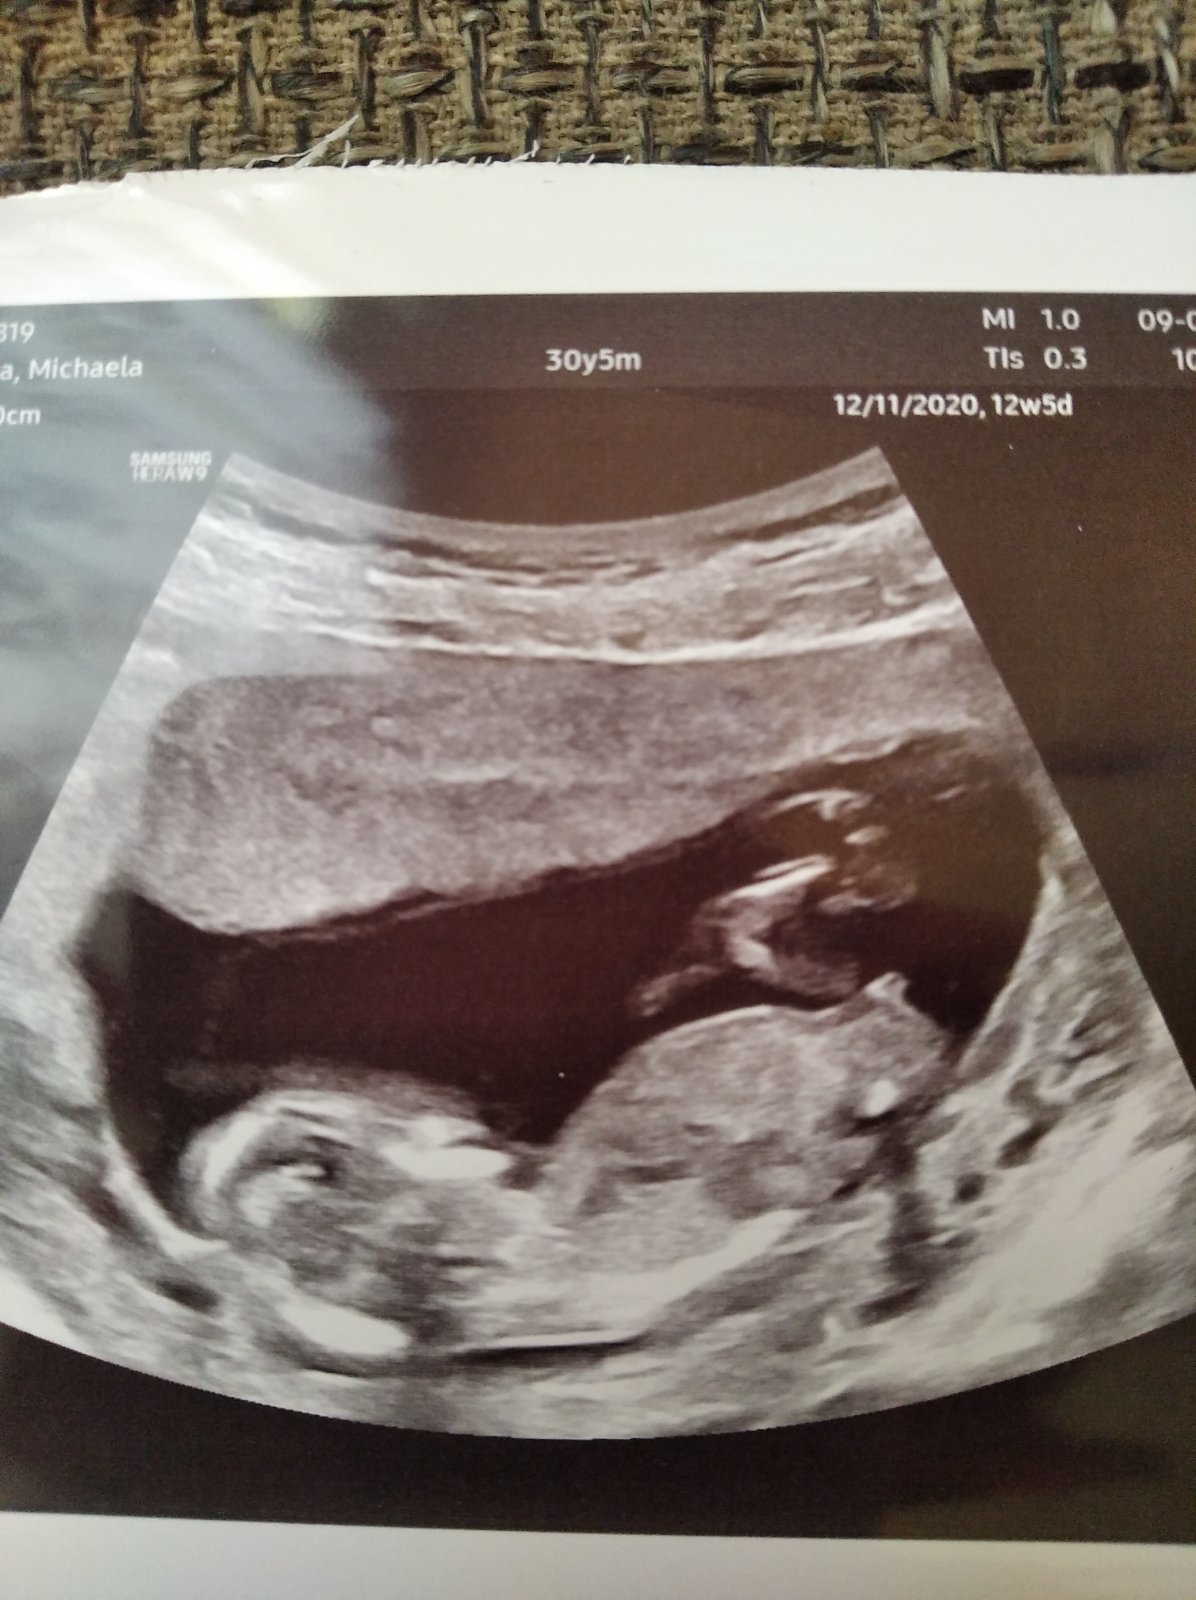

Je to kluk?

Přijde mi ten hrbolek vodorovně. Takže já říkám holka 😂

Myslím, že spíš holka. Nám u všech kluků směřoval ten hrbolek nahoru úplně

Hrbolek je vodovorovne jakoby s páteří , řekla bych, ze holka

Ano ano jak to tu už několikrát je psané, hrbolek rovně-holčička nahoru-kluk. Takže za mě taky holčička ☺️